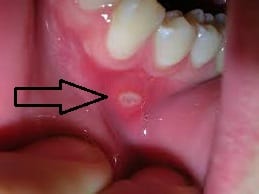

Tengo una herida en la encía, ¿Qué podría ser?

Tengo un pedacito de la encía levantada (circulo) y dura sobre el colmillo izquierdo, desconozco si me cepille muy fuerte, queme o algo por el estilo, ¿Qué podría ser? No duele nada! Y es muy pequeña.